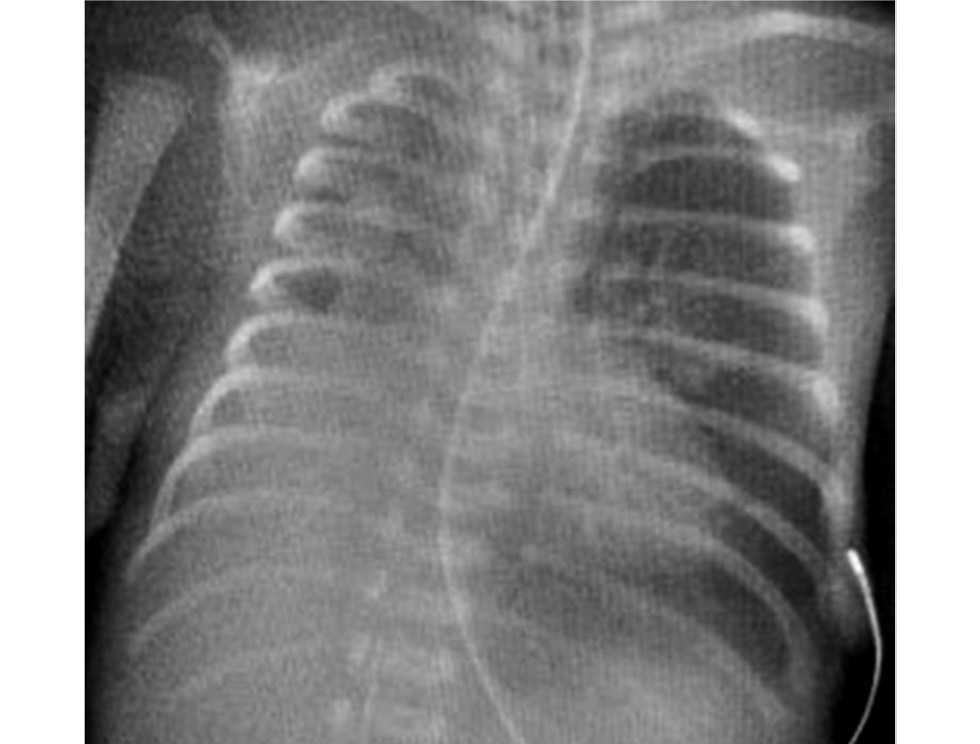

На 2 сут жизни дети были переведены в неонатальный центр на базе Детского городского многопрофильного клинического специализированного центра высоких медицинских технологий (ДГМКСЦ ВМТ) г. Санкт-Петербурга. Состояние больной требовало высокочастотной вентиляции лёгких, массивной антибактериальной терапии препаратами резерва, коррекции гипокоагуляционного синдрома и анемии. По совокупности анамнестических, клинических и лабораторных данных зарегистрирован ранний неонатальный сепсис, респираторный дистресс-синдром с выраженным снижением пневматизации обоих лёгких (рис. 1). По данным эхокардиографии выявлены открытый артериальный проток и высокая лёгочная гипертензия. К терапии добавлены ингаляции оксида азота. По данным нейросонографии выявлены внутрижелудочковые кровоизлияния 3 степени слева и 2 степени справа. Больная обследована на течение внутриутробной инфекции: выполнены анализы крови на выявление цитомегаловируса, герпес вирусов 1 и 6 типа, микоплазмы и уреаплазмы методом полимеразной цепной реакции (ПЦР) — результаты отрицательные.

Рис. 1. Рентгенограмма органов грудной полости при поступлении (2 сут жизни).

Fig. 1. Second day of life, сhest X-ray at admission.